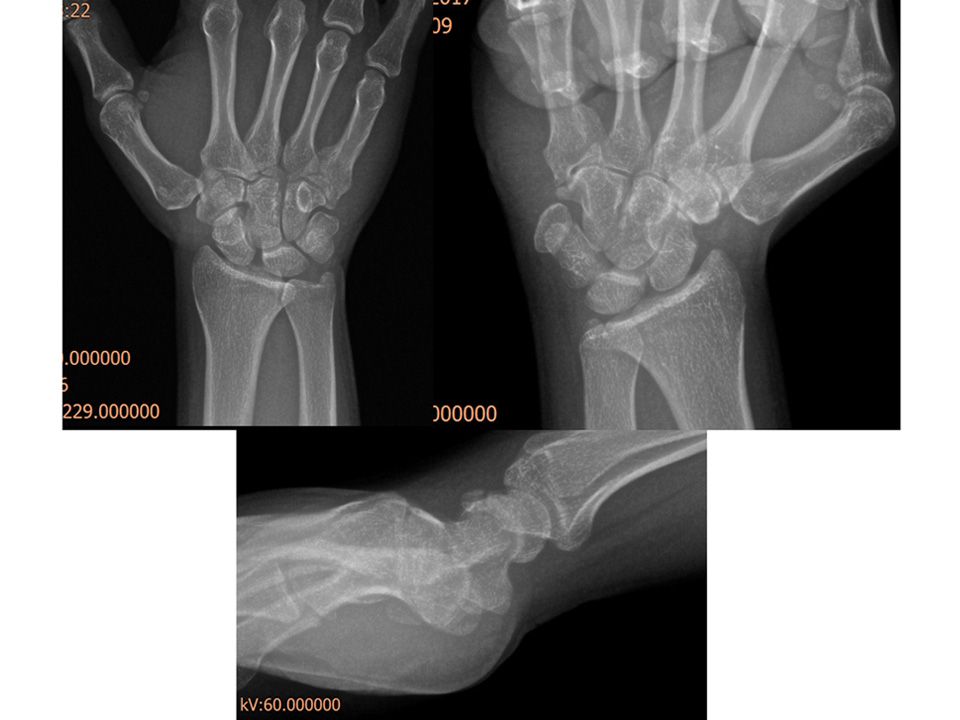

Case 11 - SL Ayrışma